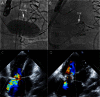

There is a growing appreciation for the adverse long-term impact of right-sided valvular dysfunction in patients with congenital heart disease. Although right-sided valvular stenosis and/or regurgitation is often better tolerated than left-sided valvular dysfunction in the short and intermediate term, the long-term consequences are numerous and include, but are not limited to, arrhythmias, heart failure, and multi-organ dysfunction. Surgical right-sided valve interventions have been performed for many decades, but the comorbidities associated with multiple surgeries are a concern. Transcatheter right-sided valve replacement is safe and effective and is being performed at an increasing number of centers around the world. It offers an alternative to traditional surgical techniques and may potentially alter the decision making process whereby valvular replacement is performed prior to the development of long-term sequelae of right-sided valvular dysfunction.